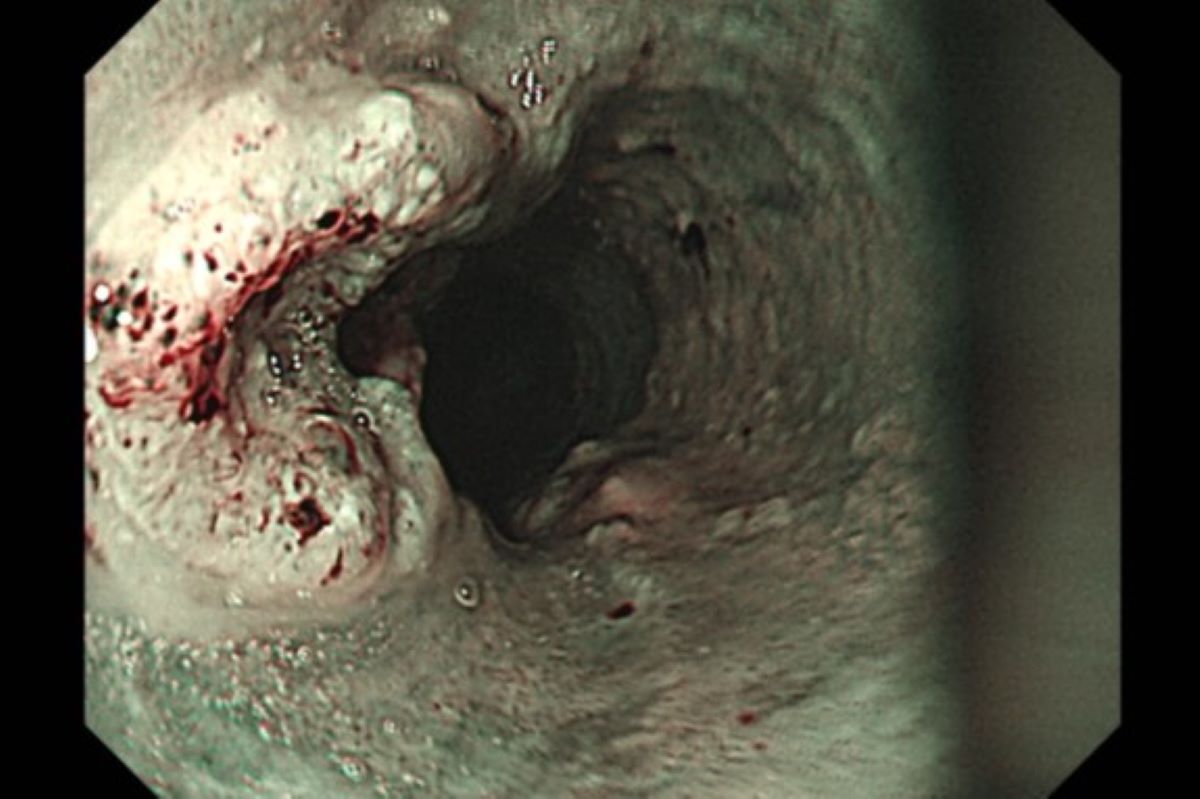

胃鏡檢查是診斷食道癌最常見的方法,可直接觀察腫瘤並切片確認,並搭配電腦斷層、全身骨掃描、腦部磁振造影、全身正子攝影評估轉移情形。洪嘉聰醫師表示,食道癌治療會依期別與病灶範圍調整方式,以手術切除為優先考量。

食道長約25至30公分,可分為頸部、上段、中段、下段,上連咽喉、下接胃部,外層為肌肉,內層覆有鱗狀上皮細胞。,食道癌分為腺癌與鱗狀細胞癌兩種,前者與胃食道逆流相關,常發生於下段或胃交界處;鱗狀細胞癌則多見於食道中段,由刺激性物質引起細胞病變,且因食道與下咽位置相近,有約5%機率合併發生癌症。